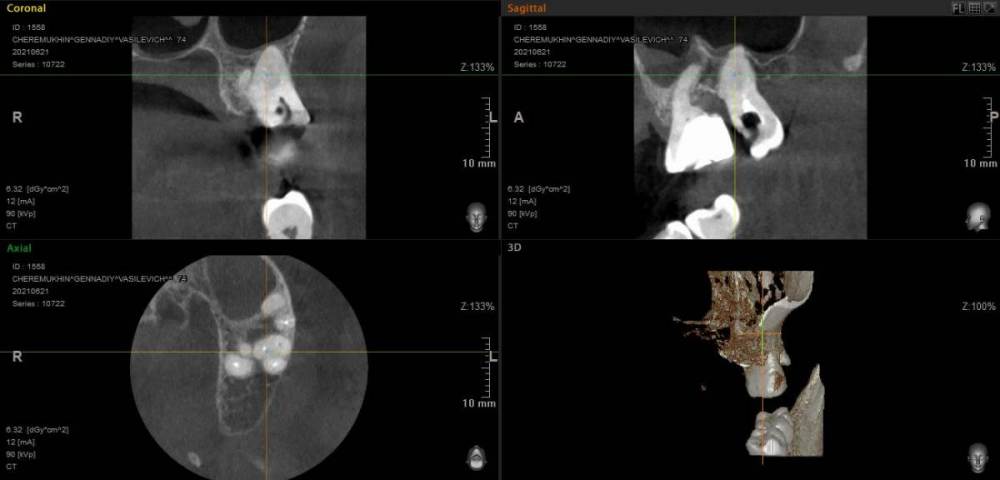

GENRY Опубликовано 6 сентября, 2021 Поделиться Опубликовано 6 сентября, 2021 Здравствуйте! Как лучше восстановить ( пусть частично) 28 зуб? Удаление не желательно т.к. с имплантацией связываться не хочу (синус лифтинг.. возраст 75 лет...) ,а опор для ортопедических конструкций нет. Кроме того боюсь, что в процессе удаления будет разрушена пломба 27 _го. Оптимизма добавляет история 27 го На орто 2012г показан 27 до его восстановления и до вмешательства в 28 зуб с добавлением в него пломбы в 2012г . Канал 28_го (небный ?) был уже запломбирован кем то раньше, скорее всего резорцин-формалиновой пастой) Доктор в 27 - м обнаружил на снимках 3 канала, наполовину прошел небный и полностью прошел дистально- щечный канал с наполнением их горячей гуттаперчей . Поскольку устье 3_го канала обнаружено не было, восстановил 27 зуб 2_мя стекловолоконными штифтами с использованием Build-It . Дистальную стенку сделал, кажется на основе пасты СПЕКТРУМ . К дальнейшей судьбе 27_го доктор отнесся скептически ( не более 2_х лет!), но похоже сработал надежно, пошел уже 10_й год, а 27 все стоит. Но 10 мес. назад выпала пломба 28 _го и он принял вид показанный на снимке. Не беспокоит. Хотелось бы повторить историю с 27_м, т.е. восстановить 28 по типу 27_го .... думаю мне хватит 5_7 лет... Регулировать нагрузки на этой стороне челюсти я научился. Сделал КТ сегмента 27_28 (В Пикассо, Vatech, просмотрщик EZ3D2009 plus ) но не смог найти ( сейчас живу в Феодосии ) терапевта работающего с этой программой. Кто то вообще не использует никакие КТ (но при этом берется за восстановление штифтом без перелечивания каналов) , кто то готов к перелечиванию, но полагается только на свои мануальные навыки, игнорируя КТ или формально глянув на пару проекций. На последней консультации добился 4-х снимков из КТ, но в общем то случайных и скорее всего не показательных.. Выкладываю скриншоты... Понял, что надо выходить за пределы городка и расширять собственное (к сожалению) понимание возможных вариантов лечения и их последствий. Вопросы по 28: 1. Если хотя бы один канал запломбирован (видимый на снимке) то это автоматически означает вскрытие камеры , а значит вскрытие и убитость содержимого (нервов, сосудов) всех остальных каналов , поскольку их устья на дне камеры? (Да, Нет, Другое) 2. Если Да, то нормально ли было пломбировать 28, не найдя и не залечив (с пломбировкой) другие каналы одновременно с небным (я имею ввиду сейчас самую раннюю пломбировку, до представленного орто) 3. Поскольку пломбировки всех каналов (сколько их ?) точно не было, то за эти 10-15 (?) лет (уже сейчас зуб стоит открытым почти год (ковид, консультации..)) должен развится пульпит, периодонтит... ? Или не обязательно? Ничего не болело, никаких выделений не было 4. Есть ли признаки какой либо хроники, воспалений в тканях на снимках? 5. Если ткани зуба и около него в порядке, то может не обязательно перелечивать все каналы, чтобы не ослаблять зуб? А только те, в которые будут вставлены штифты? Вкладка, похоже исключается т.к. феррул не замкнут на стыке с 27 зубом. 6. Есть ли какие либо оценки минимального количества требуемых штифтов ? 7 . Поскольку за 4 консультации я так и не получил ответов и снимков срезов (по КТ )показывающих количество и топологию корней и каналов, то придется добывать эту информацию самому. Буду благодарен за ссылки на материалы показывающих как это делается т.е. в каких из 3 проекций, при каком положении осей и.т.п. Я нашел только хороший ролик Ервандяна А.Г., но мне недостаточно, не хватает знания топологии зубов. Спасибо за внимание. Ссылка на комментарий